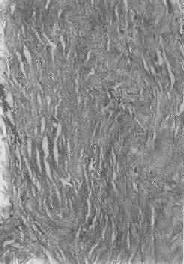

1.结缔组织玻璃样变:常见于纤维瘢痕组织、纤维化的肾小球,以及动脉粥样硬化的纤维性瘢块等。此时纤维细胞明显变少,胶原纤维增粗并互相融合成为梁状、带状或片状的半透明均质,失去纤维性结构(图1-19)。质地坚韧,缺乏弹性。玻璃样变的发生机制尚不甚清楚,有人认为在纤维瘢痕老化过程中,原胶原蛋白分子的交联增多,胶原原纤维也互相融合,其间并有较多的糖蛋白积聚,形成所谓玻璃样物质;也有人认为可能由于缺氧、炎症等原因,造成局部pH升高或温度升高,致使原胶原蛋白分子变性成明胶并互相融合所致。

图1-19 纤维瘢痕组织的玻璃样变

>胶原纤维变粗,互相融合呈均质梁状×320